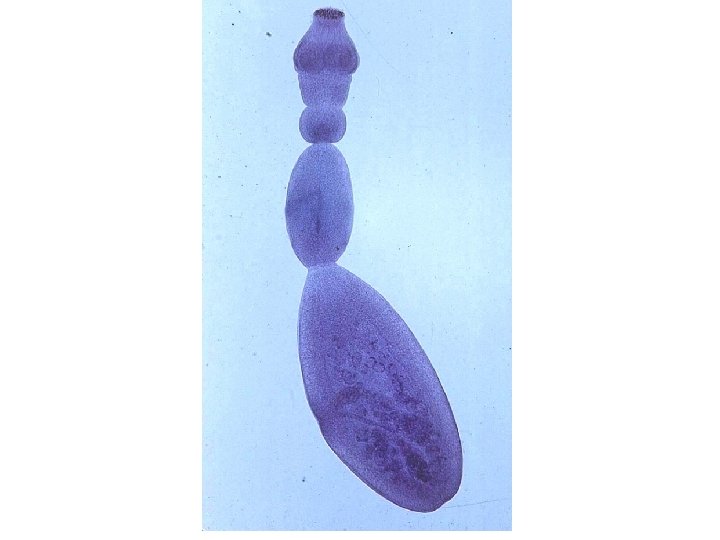

Ecchinococcus granulosus stages Raed Z. Ahmed, Medical Parasitology Lab. , 2012